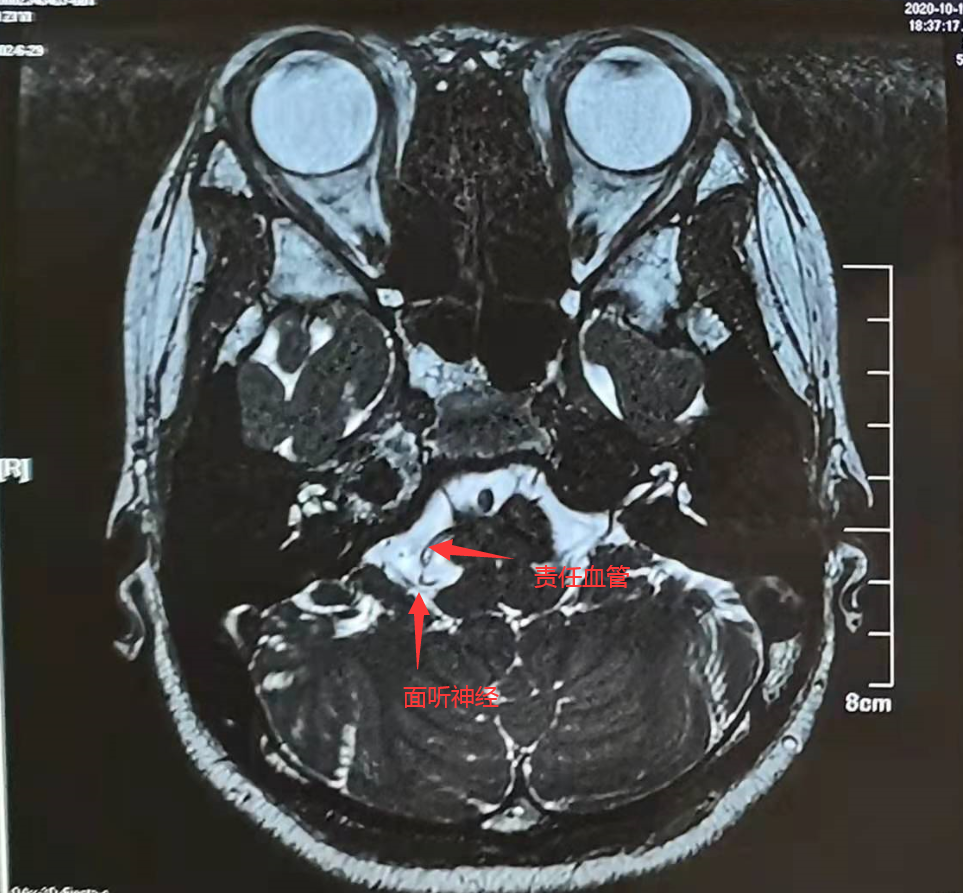

术前核磁共振检查肌电图结果mvd术解除"责任血管"压迫助她重新找回"

图片尺寸963x893